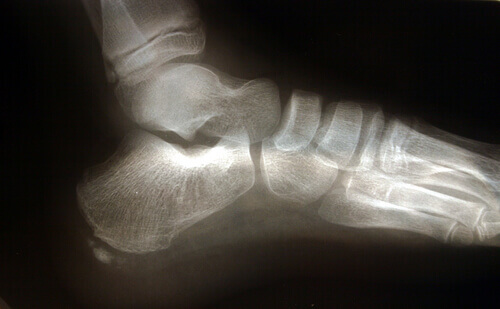

Det er flere anatomiske strukturer som spiller en rolle i overbelastning av plantarfascien. Akillessenen er et ligament som forbinder gastrocnemius-musklene, kjent som leggmuskelen og flyndremuskelen (soleus), til hælbeinet. En tilbaketrekking av akillessenen utløser en økning i trykk på hælbeinet, med den resulterende økningen av presset på plantarfascien.

En annen faktor å huske på i den anatomiske strukturen er løpesteget, eller med andre ord hvordan foten berører bakken. Plattføtter eller føtter med en tendens til å overpronere strekker plantarfascien mer, og øker dermed risikoen for rifter på grunn av det ekstra trykket på vevet.

Plantar fasciitt er ofte forbundet med tilstedeværelsen av ekstra ben, selv om det ikke er en avgjørende faktor. Når plantarfascien er forlenget over tid eller ikke behandles riktig, kan personen se endringer i gangen, noe som fører til problemer og smerter i knærne, ryggen eller nakken.